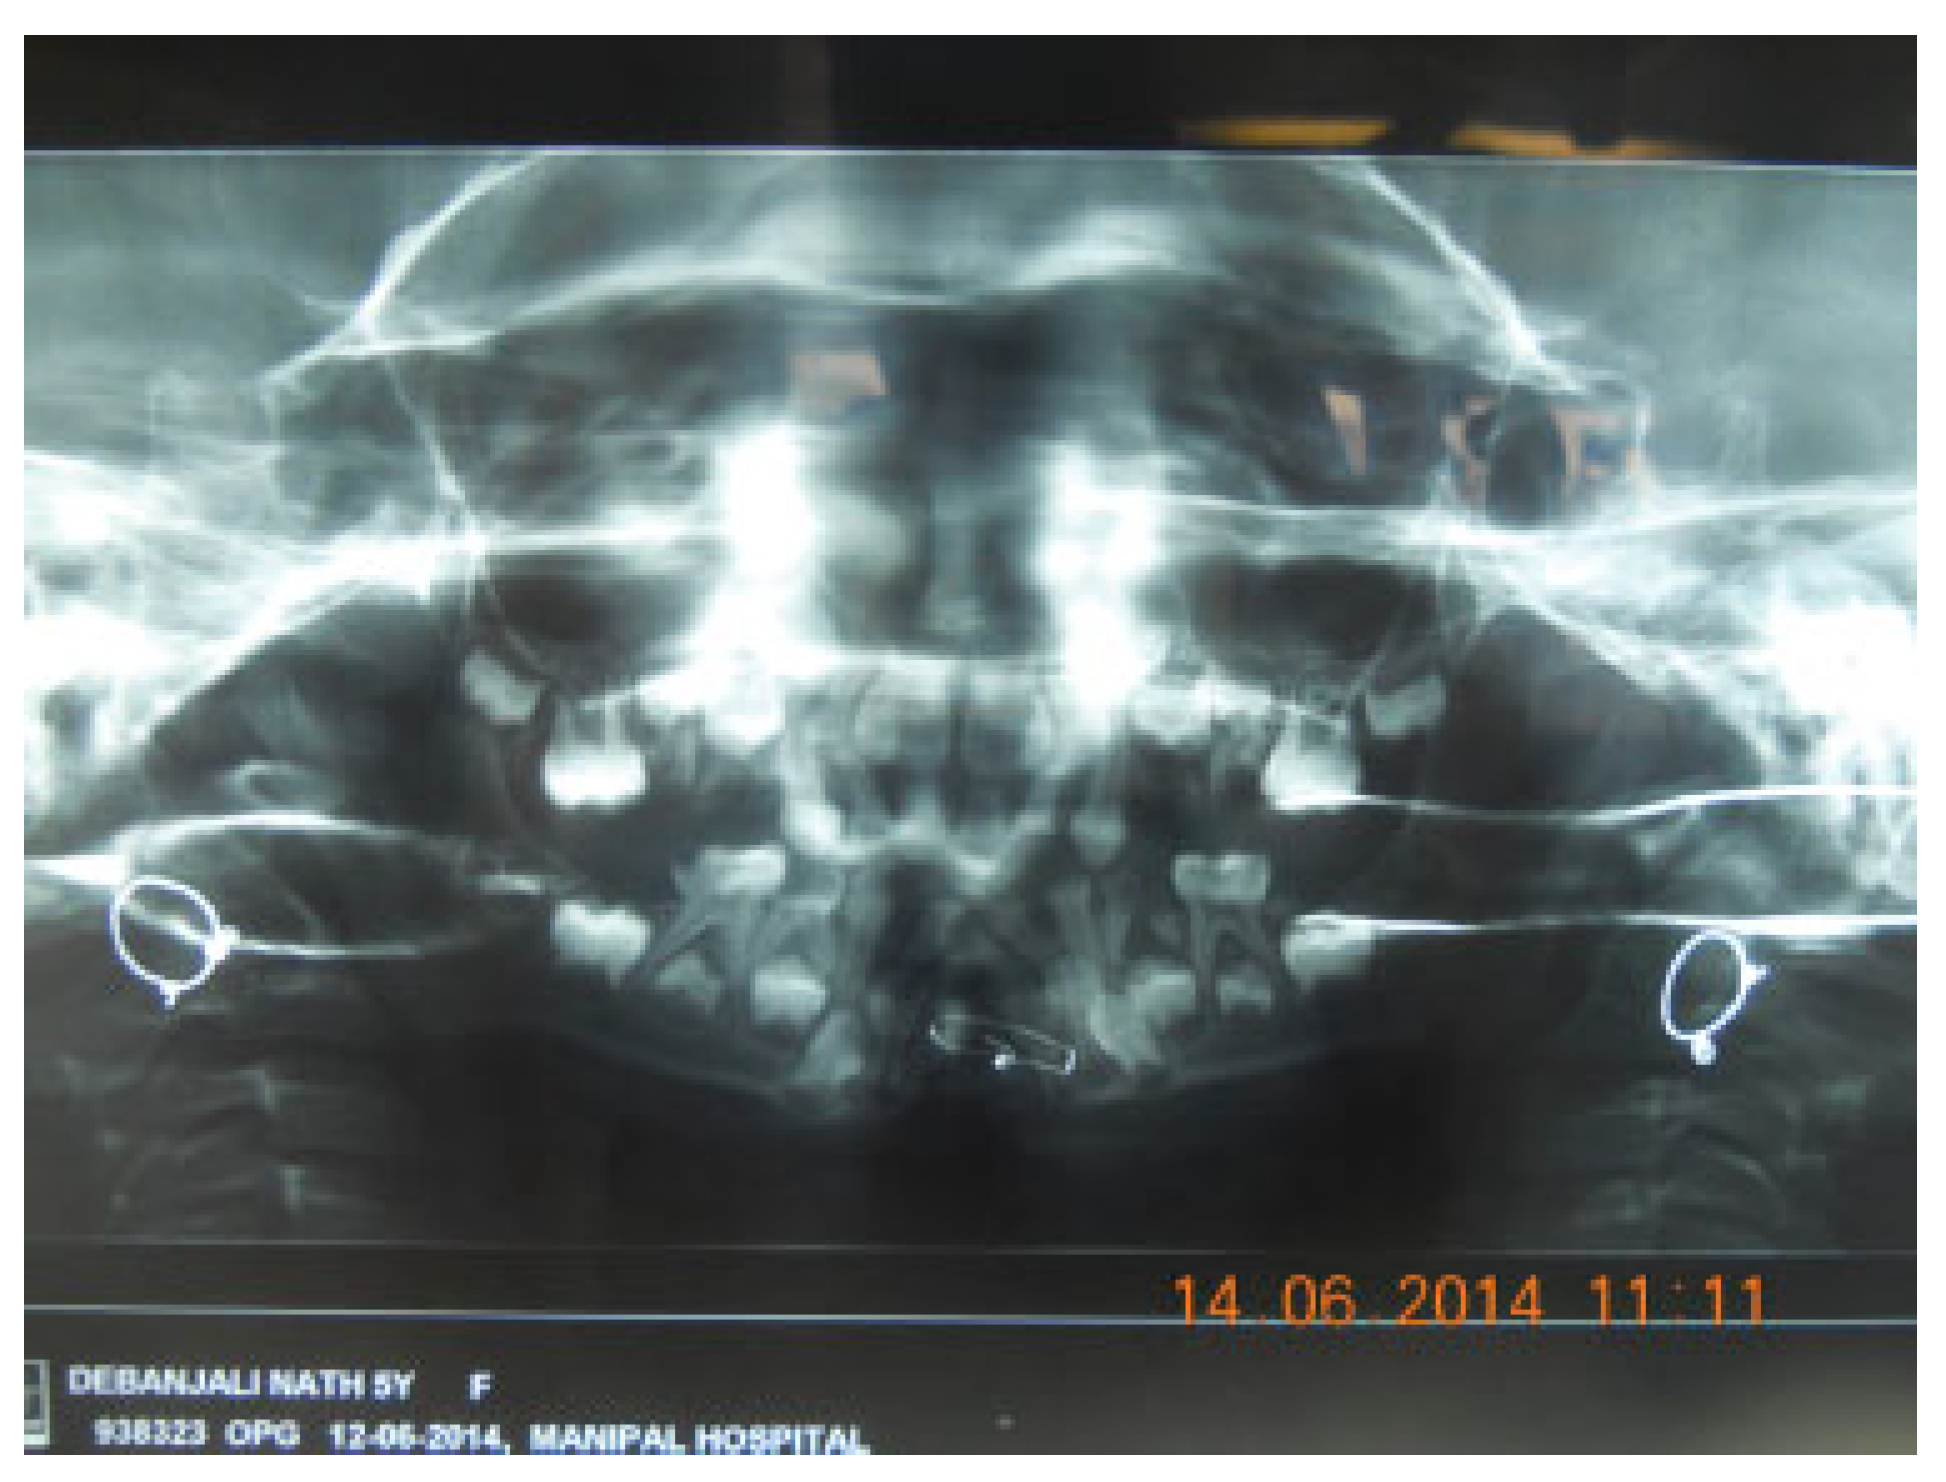

Complete Midline Cleft of Lower Lip, Mandible, Tongue, Floor of Mouth with Neck Contracture: A Case Report and Review of Literature

Case Report